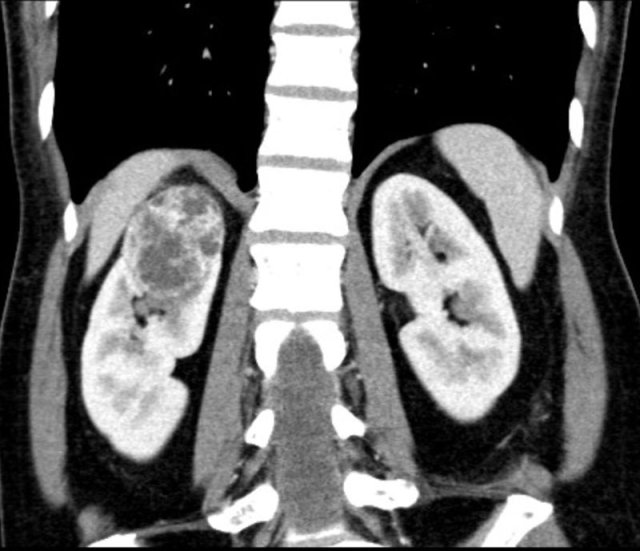

case 1

CT of a solid lesion with smaller cystic/necrotic components.

As more than 25% of the mass is composed of solid tissue this likely represents a necrotic mass in stead of a cystic lesion.

Bosniak criteria should not be used.